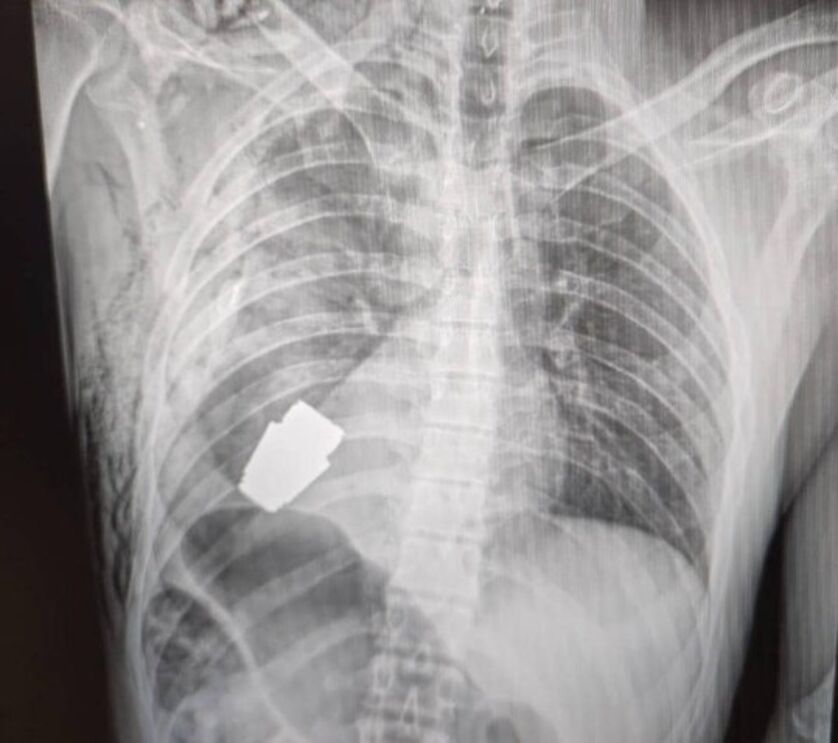

A vice-ministra da Defesa ucraniana, Hanna Maliar, partilhou na sua página de Facebook um imagens de um raio-x onde é possível ver a munição alocada no peito do soldado: "Médicos militares realizaram uma operação para retirar uma granada VOG, que não deflagrou, do corpo do soldado", descreveu.

Este tipo de granada tem um calibre de 40 mm e é disparada a partir de lança-granadas colocados em armas de assalto.